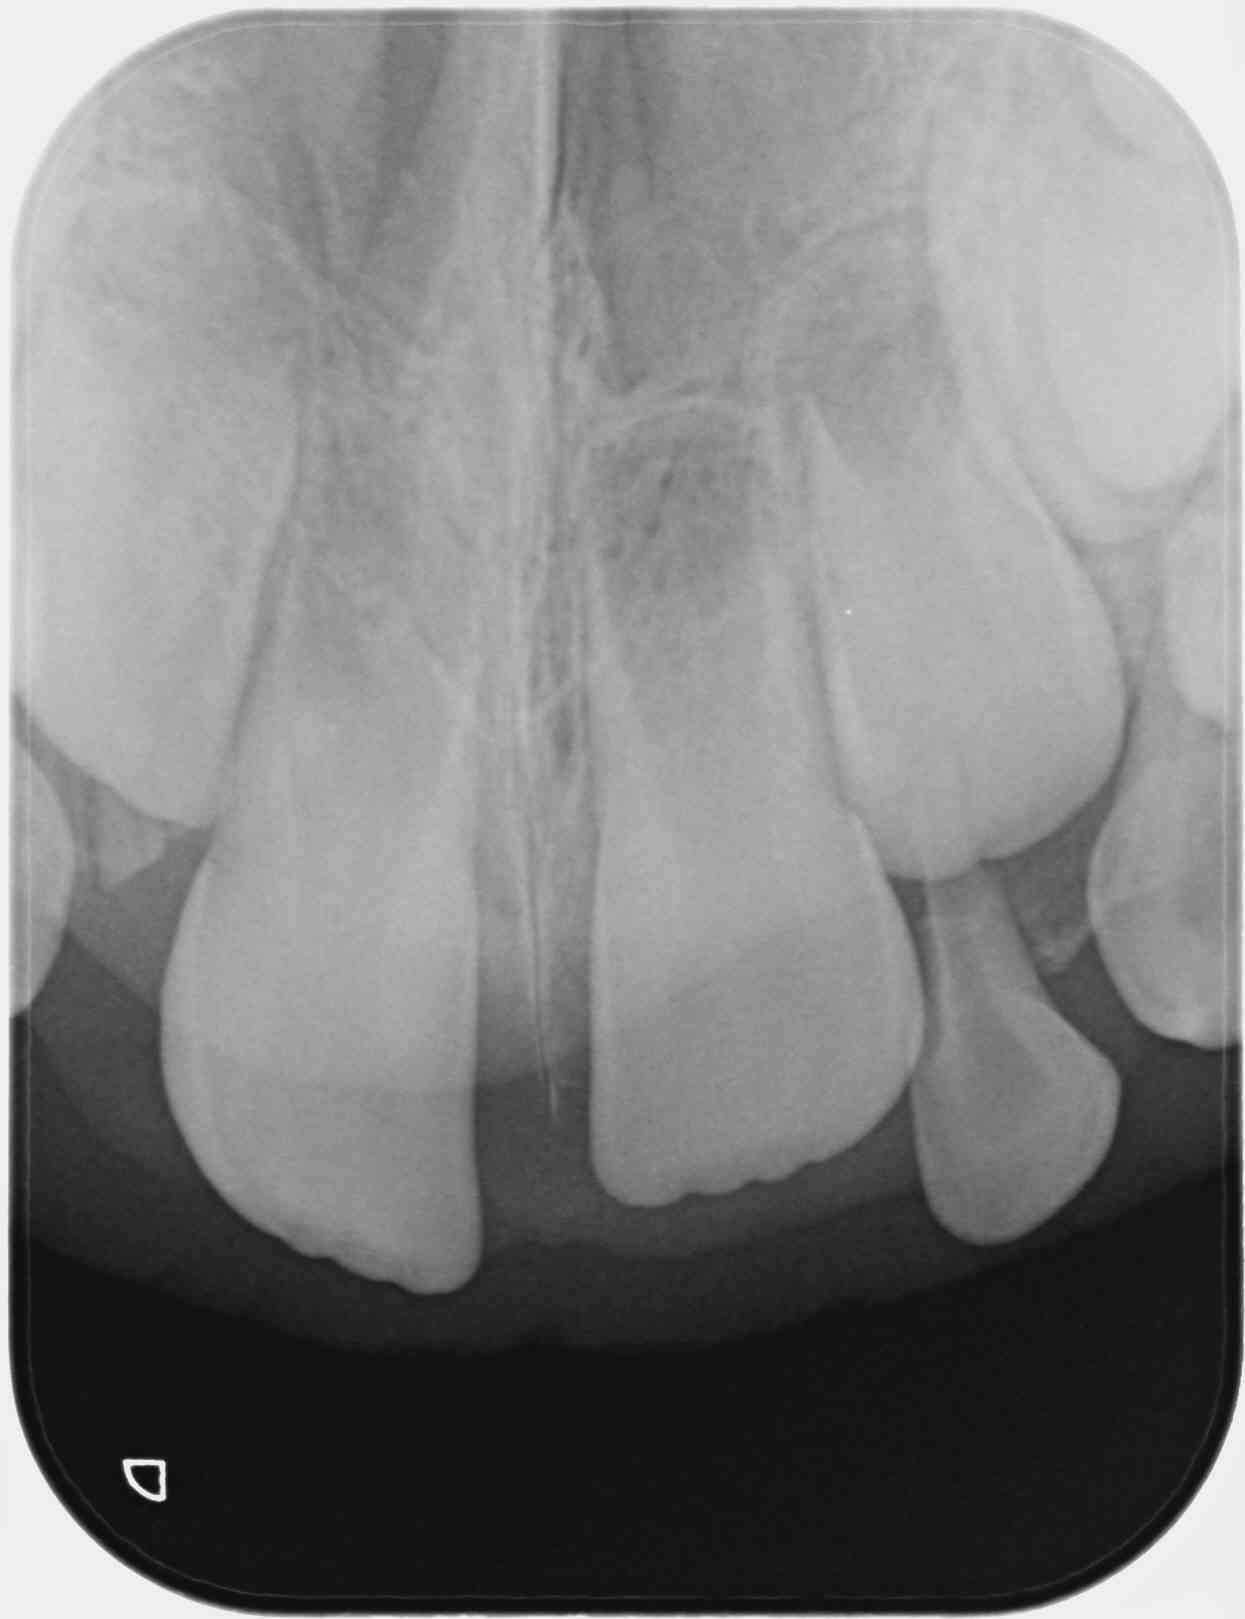

Garçon de 2 ans 11 mois, chute sur la face, peu de douleur, pas de mobilité, saignement sillon de 51.

Je ne vois rien de particulier à la radio.

Diagnostic de concussion je pense,

Il faudrait l'avis d'un pédo, mais en ce qui me concerne dans ce cas je fais une simple surveillance tous les 6 mois, y compris radiographique. Ce genre de trauma est extrêmement fréquent, les minéralisations ou nécrose des incisives lactéales consécutives sont aussi forcément très fréquentes. Les complications sont rares car la nature est plutôt bien faite sur ce coup là. La complication la plus évidente est un réveil infectieux aigu ou l'apparition d'une parulie (fistule) à l'apex, la plus vicieuse est la formation d'un granulome/kyste sans aucun symptôme clinique, avec déviation du germe de la centrale, indiquant l'avulsion de la dent lactéale concernée. Vu une fois en 12 ans.

Trauma à 2 ans, rvg à l'âge de 3 ans puis 5 ans (avulsion indiquée) puis à 7 ans.